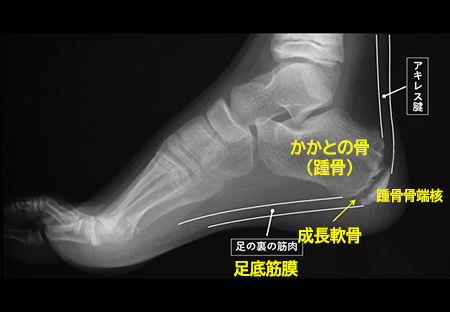

発育期の子どもの骨は、大人と違い、骨が成長していく部分 (骨端線あるいは成長軟骨と言います)が残っています。

(図の矢印)。

骨端線は物理的に弱く、かかとの部分の骨 (踵骨:しょうこつ)には、アキレス腱と足の裏の筋肉がついているため、運動で繰り返し骨端線の周囲にひっぱる力が加わることで、炎症を起こしたり、骨に細かい傷がついたりすることが痛みの原因と言われています。